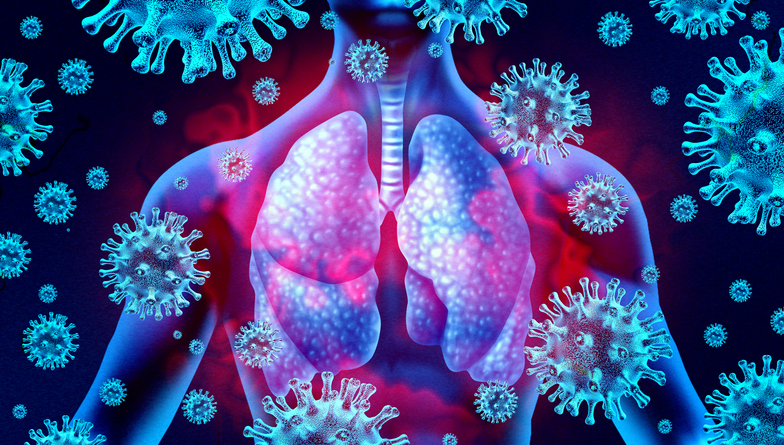

Coronavirus disease (COVID-19) leaves the lungs of people who succumbed to the disease completely damaged, and that those who stayed with it for more than a month can face potential lung problems, according to a study done by an expert in UK.

Cardiovascular Science Professor Mauro Giacca of King’s College London said that the virus has created an unrecognizable impact on patients who were in the intensive care unit for more than a month. He said that in their autopsy; they found that the lungs of the victims were disrupted completely, and that in some cases, one cannot distinguish that it used to be a lung.

“There are large numbers of very big fused cells which are virus positive with as many as 10, 15 nuclei. I am convinced this explains the unique pathology of COVID-19. This is not a disease caused by a virus which kills cells, which had profound implications for therapy,” he told The Guardian.

Giacca said that such findings also showed “real problems” that COVID-19 survivors may face.